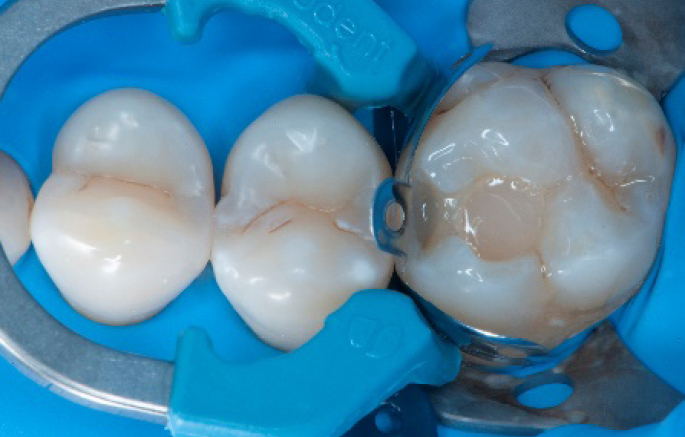

Step 11:

Occlusal surface restored using Spectra ST4 composite in shade A2.

Step 12:

The situation after rubber dam removal.

Step 13:

Occlusal check

Step 14:

2 weeks control